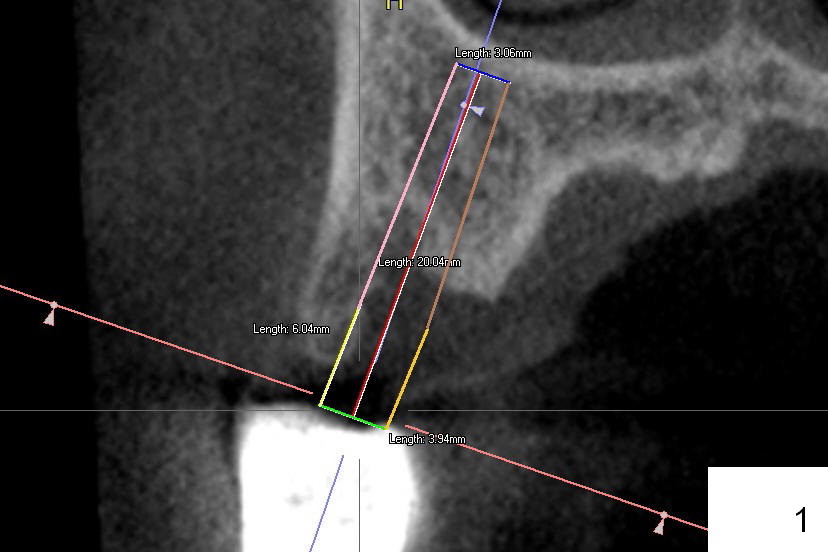

A 57-year-old man has history of chronic periodontitis.  The tooth #3 had been lost and the teeth #4 and 5 were extracted 5 years ago.  CT taken post extraction shows a palatal defect at #4.  The implants at #3 and 5 were placed a month prior to that at #4 (Fig.2 (4.5x14 mm); 2 years ago).  A splinted provisional was fabricated between #3 and 5, half month post #4 implant placement.  Final restorations were cemented 4 months later.